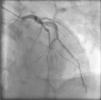

Case reportA 61-year-old man with no history of cardiac disease presented to a community hospital reporting typical chest pain 3hours in duration with more severe intensity in the last 30minutes. The initial standard 12-lead electrocardiogram (ECG) showed ST-segment elevation in leads V1–V5 and slight ST-segment elevation in the inferior leads (Fig. 1A). The patient was given 5000U of unfractionated heparin IV, 600mg clopidogrel oral loading dose and 300mg oral aspirin, and was transferred to our hospital for urgent catheterization. He arrived at our cath lab hemodynamically stable, with persistent chest pain. Coronary angiography, performed four and a half hours after symptom onset, showed a normal left coronary artery (Fig. 2) and patent main vessel of the codominant RCA. Left ventriculography was normal. Careful review of the coronary angiogram revealed proximal occlusion of the right ventricular (RV) branch of the RCA (Fig. 3A and B). The RV branch occlusion was managed with balloon dilation and stenting (2.0mm×12.0mm bare-metal stent at 16atm, Multi-Link Mini Vision®, Abbott Vascular, USA), resulting in resolution of the chest pain and ST-segment elevation (Figs. 1B and 3C). One hour after the procedure the patient experienced a new episode of chest discomfort and ST-segment changes similar to the initial ECG (re-elevation in leads V1–V4 and slight elevation in leads II, III, and aVF) (Fig. 1C). Emergency coronary angiography demonstrated acute stent thrombosis, which was probably related to previous inadequate stent covering of the proximal portion of the coronary plaque. Abciximab infusion was initiated, thrombus aspiration was performed and another proximal and overlapped bare-metal stent (2.25mm×12.0mm at 12atm, Multi-Link Mini Vision®, Abbott Vascular, USA) was implanted, again resulting in resolution of chest pain and ST-segment elevation. The peak troponin I level was 5.2ng/ml. The patient recovered without sequelae and was asymptomatic and fully active one month later. Contrast-enhanced magnetic resonance imaging (MRI) performed 30 days after presentation showed normal left ventricular function and normal right ventricular size and motion. No area of delayed hyperenhancement was visualized (Fig. 4).